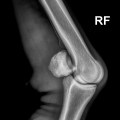

เอ็กซเรย์ดิจิตอล

เอ็กซเรย์ถือเป็นเครื่องมือพื้นฐานในการตรวจอาการบาดเจ็บของกระดูก และข้อในม้า ปัจจุบันสามารถทำงานได้แม้ในพื้นที่่ห่างไกลที่ไม่มีไฟฟ้า และทราบผลการตรวจได้ทันที